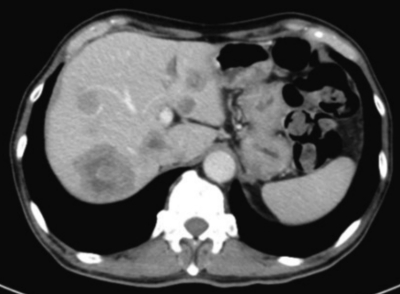

血液所見:赤血球 385 万、Hb 10.9 g/dL、Ht 37 %、白血球 5,100、血小板 14 万。血液生化学所見:総蛋白 7.2 g/dL、総ビリルビン1.1 mg/dL、AST 54 U/L、ALT 48 U/L、ALP 722 U/L(基準 115〜359)、γ-GTP 264 U/L (基準 8〜50)、CEA 78 ng/mL (基準 5以下)、CA19-9 350 U/mL(基準 37以下)。CRP 2.8 mg/dL。腹部造影CTを別に示す。